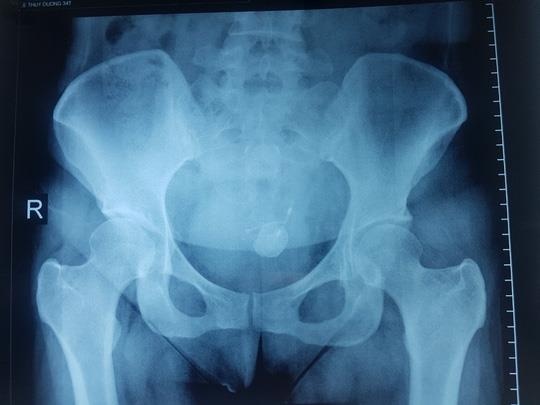

Qua thăm khám, kiểm tra, các bác sĩ phát hiện trong bàng quang có sỏi to bằng ngón chân cái (hơn 2,2 cm) bao quanh một dị vật chữ T, một phần của vòng chữ T nằm trong ổ bụng.

| Dị vật đóng sỏi trong bàng quang nữ bệnh nhân. Ảnh: Người Lao Động. |

Như chị D., một nhánh vòng tránh thai đâm xuyên thành bàng quang và giữ lại tại đó, qua nhiều năm đã hình thành sỏi trong bàng quang gây ra các rối loạn của đường tiết niệu.

Chị D. đặt vòng tránh thai cách đây hơn 8 năm nhưng không biết chiếc vòng chữ T này xuyên cổ tử cung chui vào trong ổ bụng rồi chui vào bàng quang.